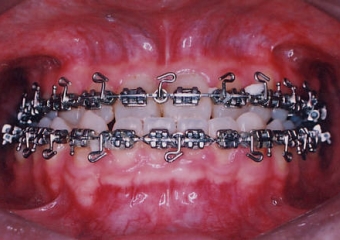

Mordida após a cirurgia